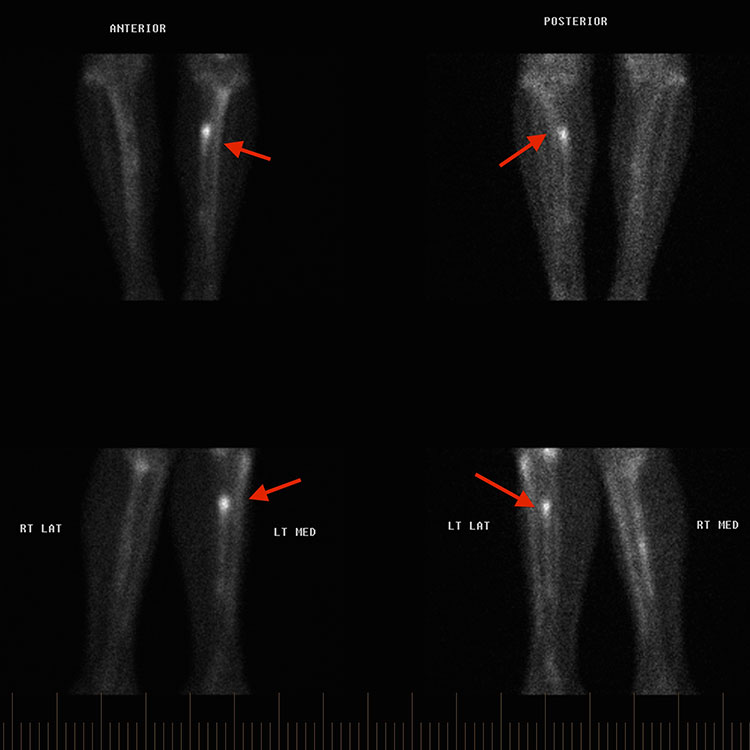

ΣΑΡΩΣΗ ΟΣΤΩΝ

Η σάρωση οστών ή το σπινθηρογράφημα πυρηνικής ιατρικής χρησιμοποιεί την έγχυση ενός ραδιοσημασμένου ισοτόπου (συνήθως Technetium-99). Αυτή η τεχνική είναι πολύ ευαίσθητη για την ανίχνευση αυξημένης οστικής αναδιαμόρφωσης. Η πρόσληψη ραδιοϊσοτόπων παραμένει για μια χρονική περίοδο πέρα από την κλινική αποκατάσταση των καταγμάτων στρες και έτσι η σάρωση οστών μπορεί να είναι λιγότερο χρήσιμη στη συνεχή παρακολούθηση της ανάρρωσης. Επίσης, η αυξημένη πρόσληψη ισοτόπων δεν είναι ειδική για ένα κάταγμα στρες καθώς μπορεί να υπάρχουν άλλες αιτίες (συμπεριλαμβανομένης της μόλυνσης ή του όγκου).

ΟΠΙΣΘΙΑ ΚNHMH

Τα κατάγματα λόγω πίεσης που αφορούν το οπίσθιο και το έσω όριο της κνήμης είναι σχετικά συχνά. Είναι επίσης σημαντικό να ληφθούν υπόψη και οι άλλες αιτίες του πόνου της κνήμης στους αθλητές. Αυτά περιλαμβάνουν το σύνδρομο χρόνιας καταπόνησης και το σύνδρομο έσω κνημιαίου στρες (νάρθηκες κνήμης).

Διερευνήσεις

Θα πρέπει να παραγγελθούν ακτινογραφίες και μπορεί να αποδείξουν νέο περιοστικό οστό. Η μαγνητική τομογραφία μπορεί να δείξει οίδημα μυελού, περιοστική αντίδραση και πιθανώς γραμμή σκληρωτικού κατάγματος. Οι αξονικές τομογραφίες μπορεί να είναι κατάλληλες για την αποσαφήνιση του βαθμού τραυματισμού των οστών ως βάση για τον προγραμματισμό αποκατάστασης.